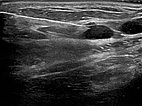

Circumscribed macrocystic malformation on the abdominal wall on ultrasound. Note the anechoic fluid in the thin-walled cystic spaces filled with liquid (lymph).

Ultrasound of the abdominal wall, a little further caudally. Here, the cystic parts of the lymphatic malformation are smaller. However, the lesion is still extraperitoneal in the abdominal wall.